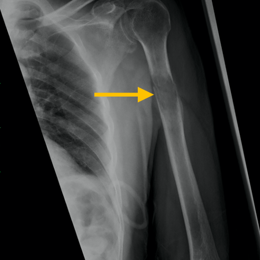

Radiographic imaging is used to help form a diagnosis of Myeloma. These include X-Ray, MRI, CT and Bone Scans.

An example of a Myeloma X-ray is shown. Myeloma may present as a diffuse osteoporosis with the bones throughout the body looking very thin on X-rays.